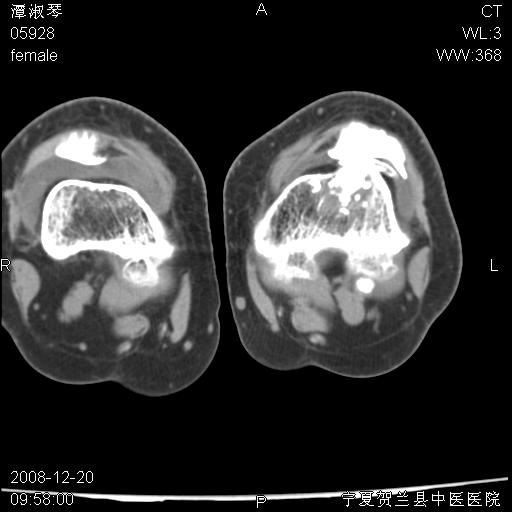

标题: CT17526:请各位看看是啥? [打印本页]

标题: CT17526:请各位看看是啥?

内生软骨瘤?骨梗死?

考虑内生软骨瘤可能性大

考虑-----骨梗死+退变

支持骨梗死,退行性骨关节病,膝关节积液.

考虑骨梗死可能性大

支持骨纤或内生软骨瘤或骨梗死,退行性骨关节病,膝关节积液.

骨梗死可能性大

左股骨下段骨梗死。双膝退变。

支持:内生软骨瘤或骨梗死!另:退行性骨关节病,膝关节积液。

左胫骨下端松质骨及髓腔内可见点片状高密度灶,骨皮质无明显膨胀及变薄。病变范围较长。支持骨梗死,退行性骨关节病,膝关节积液